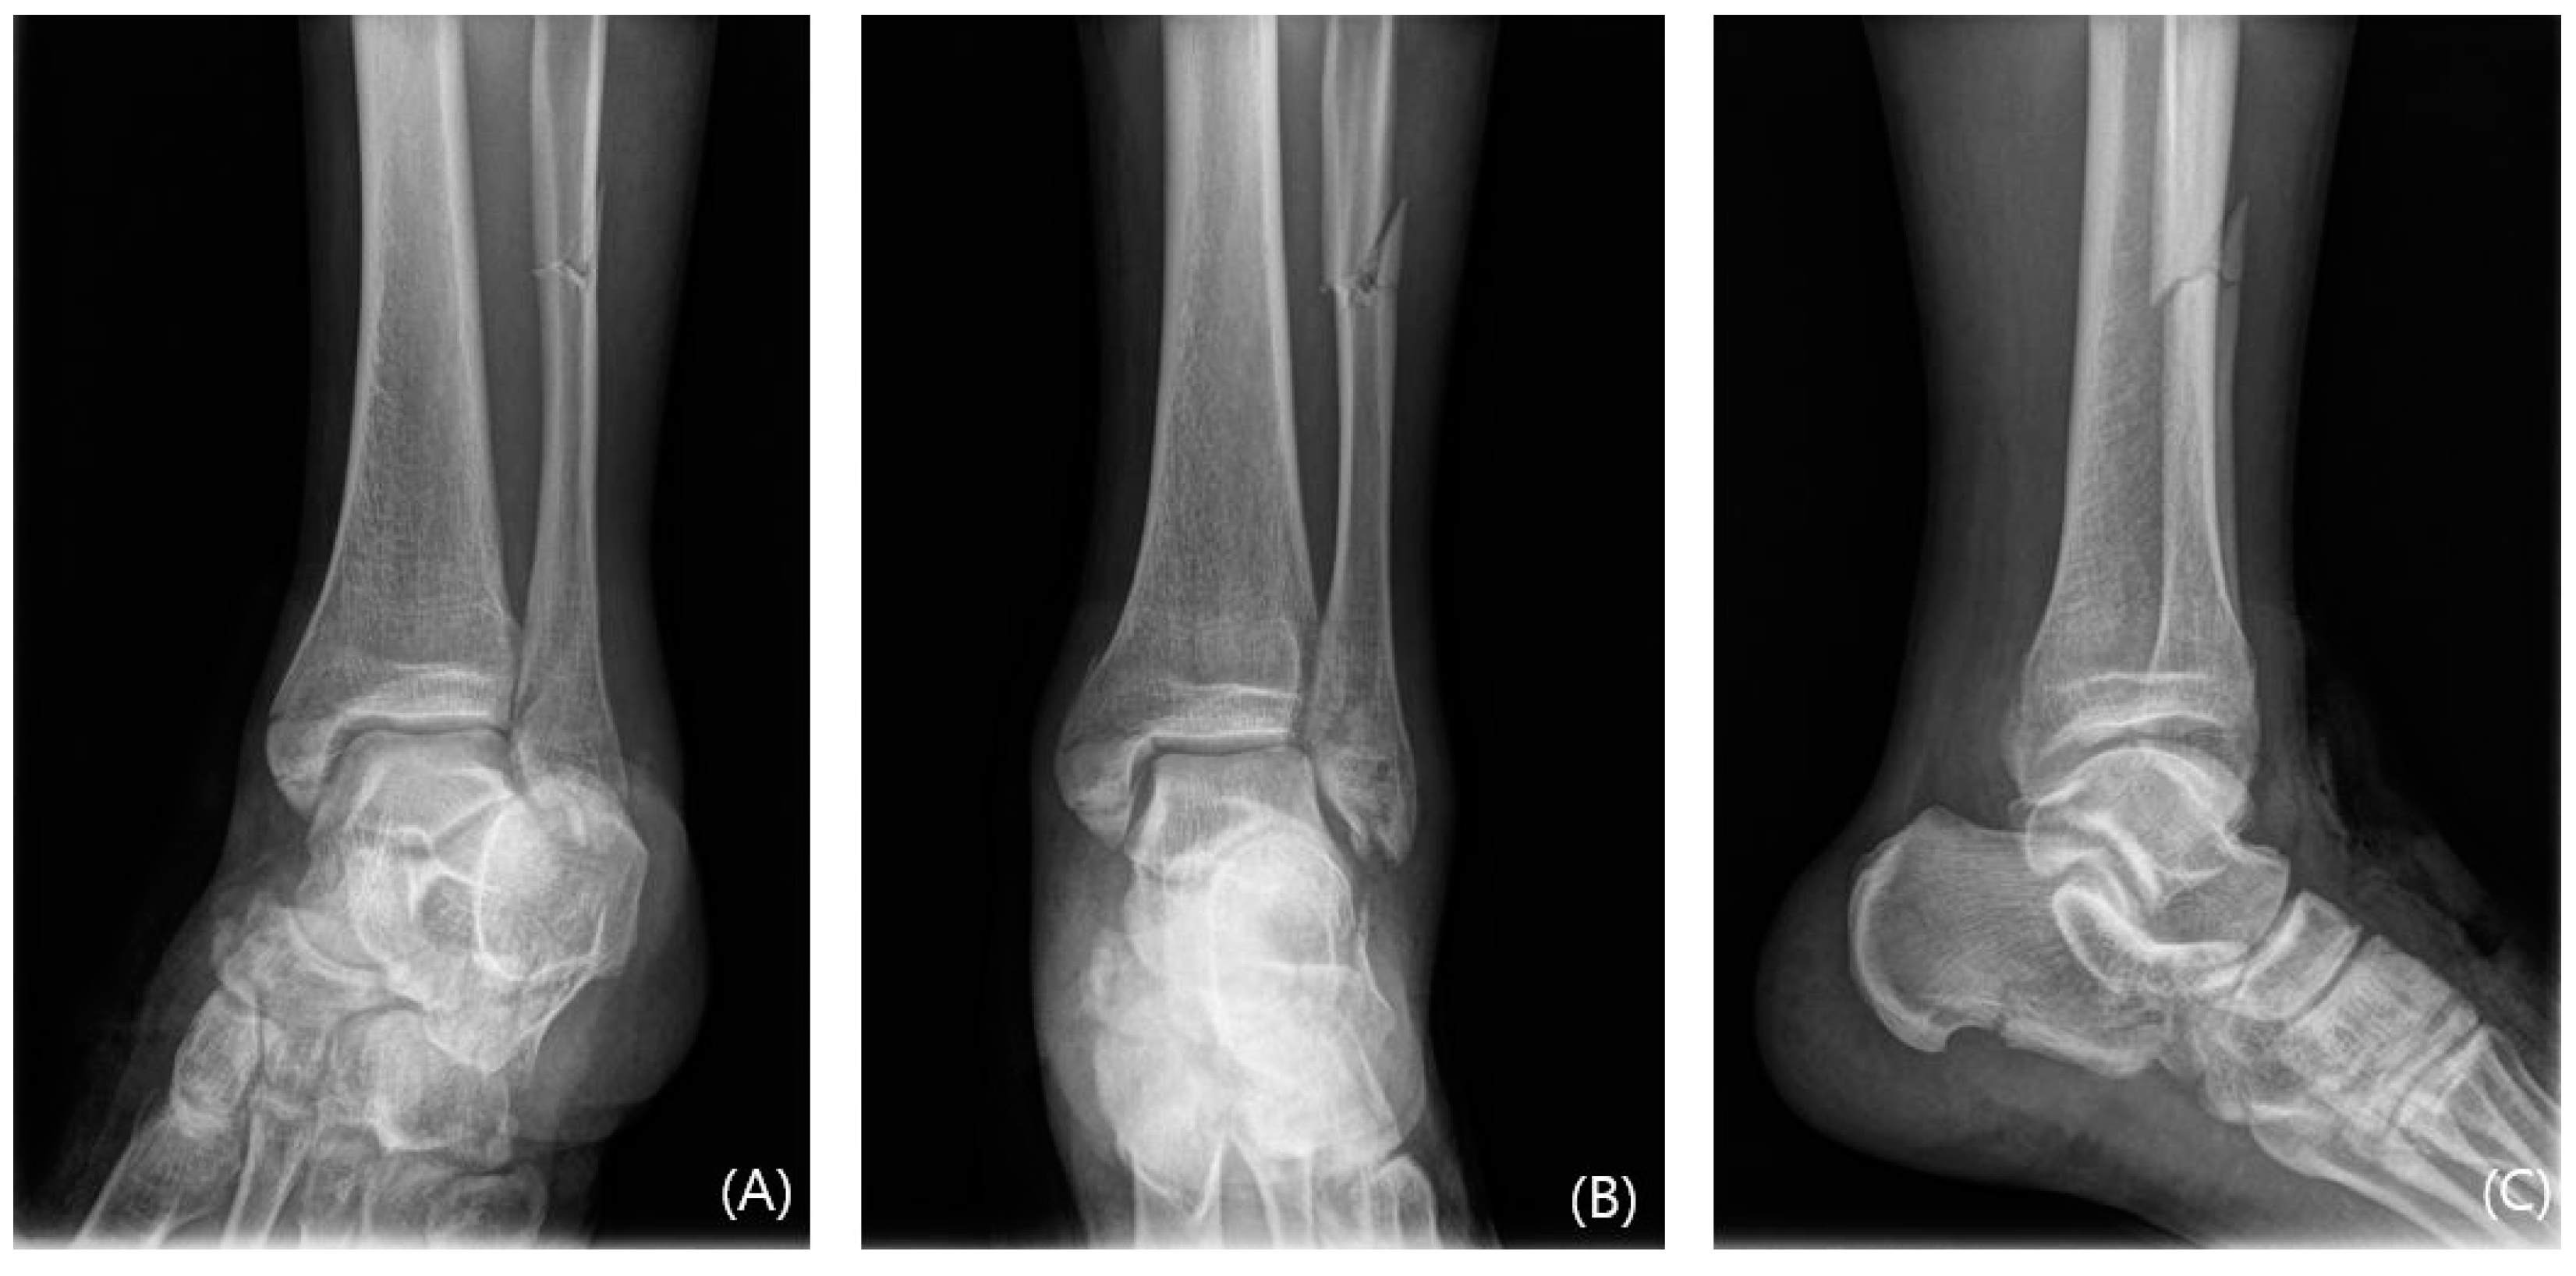

In cases of instability, a mini-plate (Arix Hand System, Jeil Medical, Seoul, Republic of Korea) is shaped to cover the Wagstaffe fracture and secured using 2.0 mm cortical screws and locking screws (Figure 3). For smaller fractures, screws were applied to the proximal and distal sections of the mini-plate at the fracture site. Screw fixation was performed at the fracture site when possible (Figure 4). Subsequently, tibiofibular joint stability was assessed through arthroscopy. Figure 5 and Figure 6 show the preoperative plain X-ray and CT images of a 47-year-old female with a Wagstaffe fracture. Figure 7 shows the postoperative plain X-ray image of a Wagstaffe fracture treated with open reduction and internal fixation using the described technique. Postoperative CT images were used to further confirm the reduction and fixation (Figure 8).

Figure 5. The preoperative mortise, anteroposterior, and lateral radiographs (AC) of a 47-year-old female with Lauge-Hansen class PER IV ankle fracture. The AITFL fibular avulsion fracture is not visible on these plain radiographs.